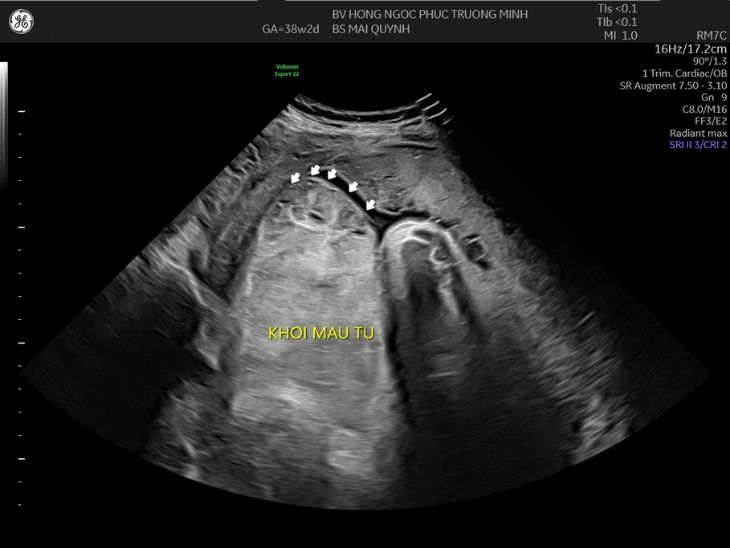

Tuy nhiên, trong quá trình siêu âm, bác sĩ phát hiện bất thường tại đáy tử cung. Theo đó, trên màn hình hiển thị, bên mép trên bánh nhau có cấu trúc lạ hồi âm kém, dạng tương tự máu đông, kích thước khoảng 113 x 97mm. Từ những hình ảnh này, bác sĩ hướng đến nhận định đây là khối máu cục do bong nhau - dấu hiệu cơ bản nhất của nhau bong non thể nặng - một biến chứng nguy hiểm trong sản khoa.

Nhau bong non thể nặng Hình ảnh siêu âm phát hiện khối máu tụ tại mép bên phải tử cung